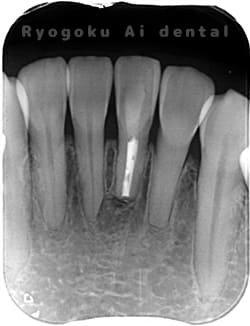

術前

-

歯根端切除術後

術後1年

- 原因

- 歯根嚢胞

- 治療内容

- 歯根端切除法

- 治療費用

- ¥77,000

他院で行った根管治療後、腫れがひかないためにご来院された患者様です。歯根端切除を行い、現在、経過良好です。